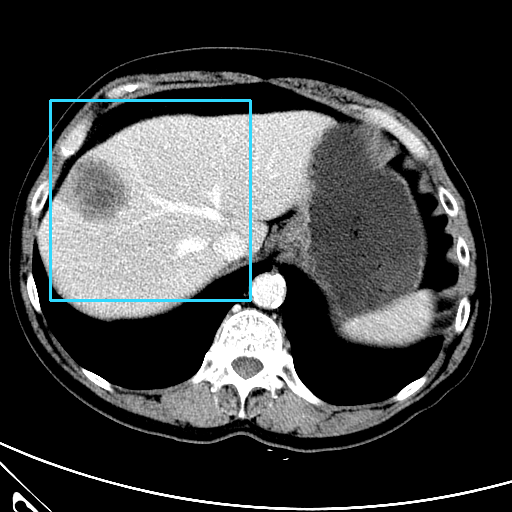

Refer to caption

CT

Zoomed

MRI

Target\mathrm{Target}

StolenEPD{\mathrm{Stolen}}^{\mathrm{D}}_{\mathrm{EP}}

StolenEPD1{\mathrm{Stolen}}^{\mathrm{D1}}_{\mathrm{EP}}

StolenITD{\mathrm{Stolen}}^{\mathrm{D}}_{\mathrm{IT}}

StolenITD1{\mathrm{Stolen}}^{\mathrm{D1}}_{\mathrm{IT}}

Figure 7: Lossy image reconstructions on CT (row 1, 2) and MRI (row 3, 4) images, where the row 2, 4 provide a zoomed-in view of the bounding box region of the row 1, 3. The leftmost column represents the target images, while the subsequent four columns show the stolen images reconstructed by the decoder D or D1 in two scenarios.

A visual comparison between target and stolen images is available in Fig. 7. We observe that the stolen images from IT Scenario closely resemble the input ones, particularly in the tumor regions, whereas stolen images from EP Scenario exhibit blurring artifacts in finer details. In both cases, the stolen images reconstructed by D1D1 demonstrate a comparable quality to those reconstructed by DD, thus further confirming the effectiveness of the reduced decoder D1D1.